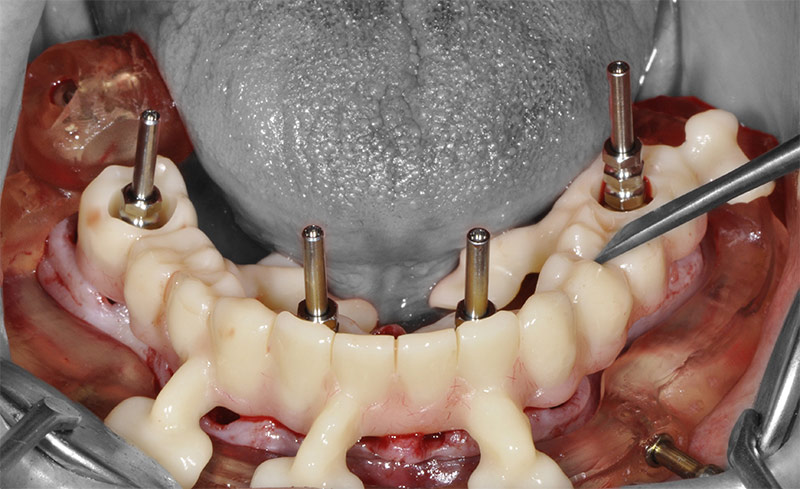

Fig. 28 : le guide de forage et d’insertion des implants est empilé sur le guide de résection laissé en place.

Fig. 29 : toujours sans toucher au guide résection, une fois les implants mis en place, les piliers prothétiques sont vissés.

Fig. 30 : enfin, la restauration transitoire est empilée sur le guide de résection pour être solidarisée en bouche aux gaines provisoires vissées sur les piliers.

Fig. 52 : le guide de forage et de mise en place des implants est empilé sur le guide de résection osseuse.

Fig. 53 : vissage des piliers prothétiques dans les implants.

Fig. 54 : transvissage des gaines temporaires sur les piliers.

Les piliers prothétiques sont immédiatement vissés dans les implants sans déposer le guide de résection osseuse ; des gaines temporaires en titane sont transvissées sur les piliers et la restauration transitoire empilée sur le guide de résection, pour être solidarisée en bouche avec une colle composite. La finition très simple est réalisée au fauteuil et le patient quitte le cabinet dès la fin de la chirurgie avec sa restauration provisoire.